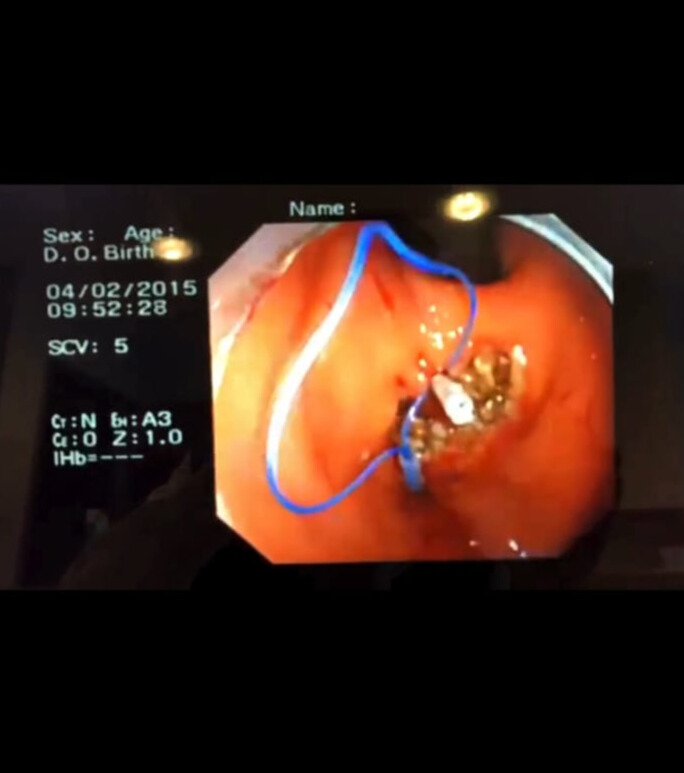

Endoloop, cerrahi prosedürlerde özellikle laparoskopik ameliyatlarda kullanılan bir ligasyon aracıdır. Temel olarak önceden hazırlanmış, emilebilir bir sütür materyalinden oluşan halka şeklinde bir bağdır. Endoloop, damar ya da doku saplarını güvenli bir şekilde bağlamak ve kesmeden önce kanamayı kontrol altına almak amacıyla kullanılır.

Endoloop, cerrahi prosedürlerde özellikle laparoskopik ameliyatlarda kullanılan bir ligasyon aracıdır. Temel olarak önceden hazırlanmış, emilebilir bir sütür materyalinden oluşan halka şeklinde bir bağdır. Endoloop, damar ya da doku saplarını güvenli bir şekilde bağlamak ve kesmeden önce kanamayı kontrol altına almak amacıyla kullanılır. Uygulama sırasında halka hedef dokuya geçirilir, ardından çekilerek sıkıştırılır ve ligasyon tamamlanır. Özellikle apendektomi, kolesistektomi gibi minimal invaziv cerrahilerde pratik, hızlı ve güvenilir bir çözüm sunduğu için tercih edilmektedir. Polip veya doku ligasyonu için tasarlanmış endoloop sistemidir. Tek kullanımlık ve steril paketlidir.

Polip rezeksiyonu sonrası kanama kontrolü veya mukozal dokuların bağlanmasında kullanılır.